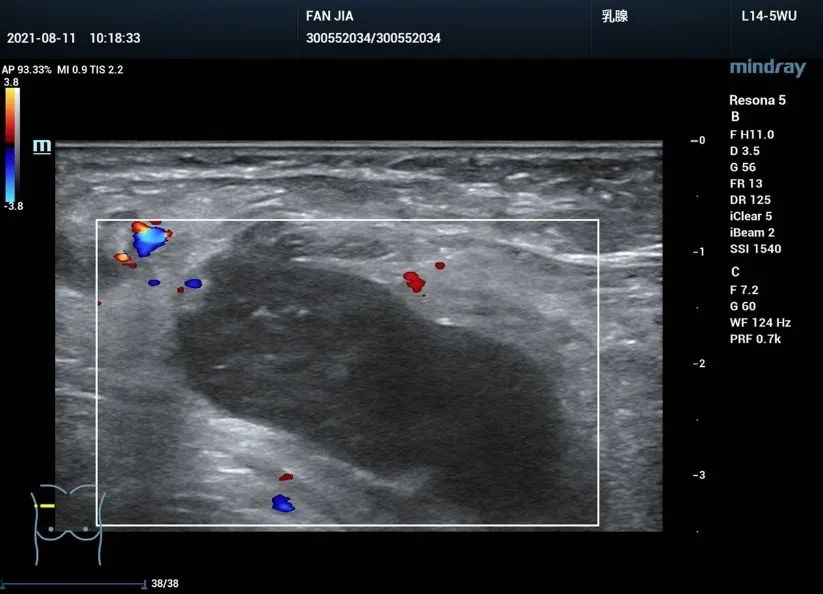

右侧肘部滑车上、右上臂近腋窝处、腋窝、右侧锁骨下可见多个低回声结节,回声减低,形态规则,边界清楚,部分淋巴门可见,部分髓质回声消失,部分淋巴结内可见类似「 筛网状 」回声,较大的淋巴结位于腋窝,大小约 3.8cmx1.5cm , CDFI:部分淋巴结内可见门型血流,部分内及周边可见少许血流信号;部分内未见明显血流信号 (图 1-6 )。

图 5 腋窝淋巴结肿大,内可见类似淋巴瘤的「 筛网状 」回声

图 6 腋窝淋巴结内未见明显血流信号